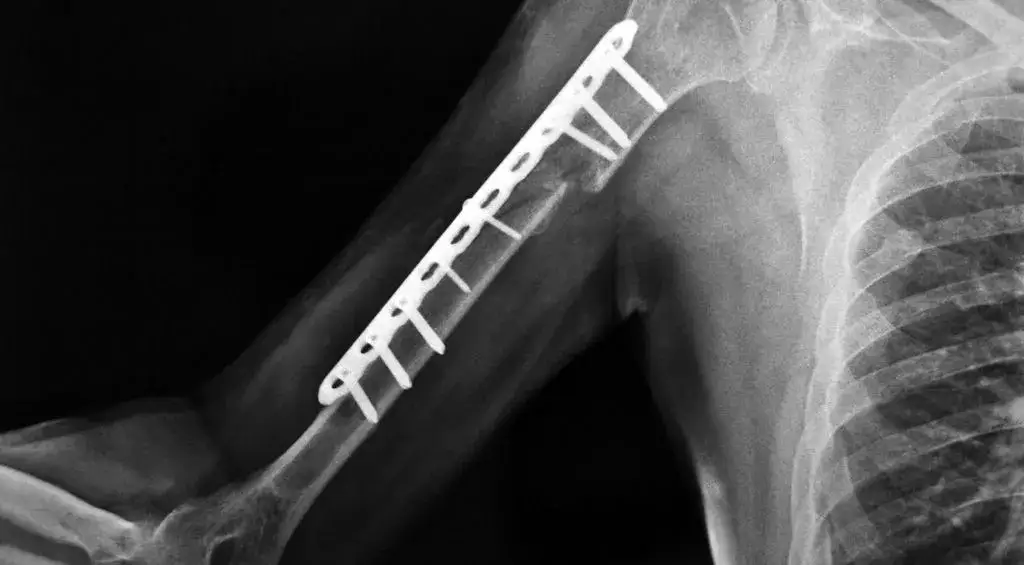

- Metoda leczenia: Czy zastosowano leczenie zachowawcze (gips, orteza) czy operacyjne (płytki, śruby, gwoździe).

Po leczeniu operacyjnym, kiedy złamanie zostało stabilnie zespolone wewnętrznie (np. za pomocą płytek i śrub), rehabilitację można i wręcz należy rozpocząć bardzo wcześnie. Często zdarza się, że pierwsze ćwiczenia wykonujemy już w pierwszej lub drugiej dobie po zabiegu, jeszcze zanim pacjent opuści szpital. Celem tych wczesnych działań jest przede wszystkim poprawa krążenia, zapobieganie groźnym zakrzepom, minimalizowanie obrzęków i przykurczów, a także utrzymanie zakresu ruchu w stawach sąsiadujących z miejscem operacji, które nie są bezpośrednio unieruchomione.

Stabilizacja wewnętrzna, czyli zastosowanie płytek, śrub, gwoździ czy drutów, to prawdziwy przełom w leczeniu złamań. Dzięki niej odłamki kostne są utrzymywane w anatomicznym położeniu, co nie tylko sprzyja prawidłowemu zrostowi, ale przede wszystkim pozwala na znacznie wcześniejsze i bezpieczniejsze rozpoczęcie ruchu. W przeciwieństwie do leczenia zachowawczego, gdzie gips całkowicie unieruchamia kończynę na długie tygodnie, stabilizacja wewnętrzna daje możliwość kontrolowanego obciążania i mobilizacji, co znacząco skraca czas rekonwalescencji i minimalizuje ryzyko utraty funkcji.